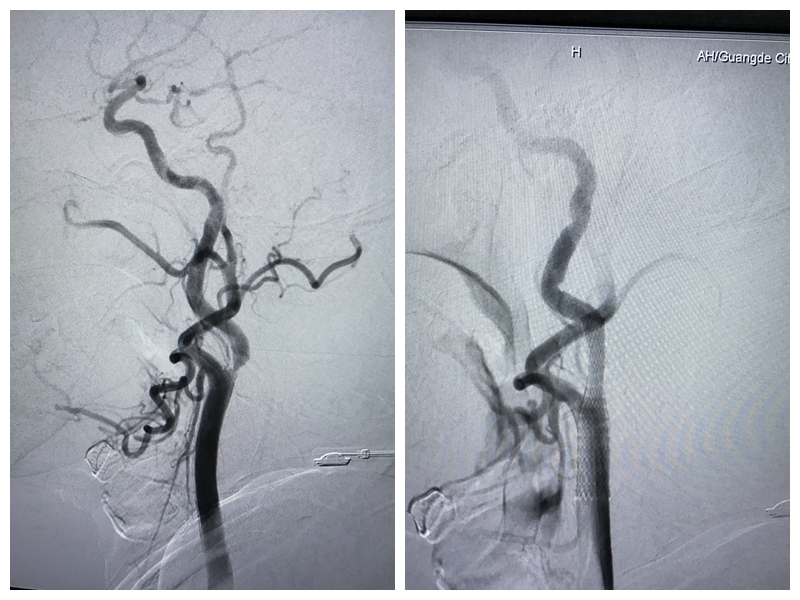

患者术前及术后的DSA对比图

颈动脉支架植入术损伤小、恢复快、治疗周期短,仅需在局麻下进行,通过一侧股动脉穿刺,在导丝导管的配合下先将保护伞放到狭窄血管远端,然后使用球囊扩张狭窄处,最后将支架放置在颈动脉狭窄处,使狭窄血管扩张,保证正常血流通过,以减少卒中风险。

我院神经内科刘勇和程斌两位副主任医师历时1.5小时,顺利完成了我市首例颈动脉支架植入术,目前该名患者术后生命体征平稳,无不良并发症。